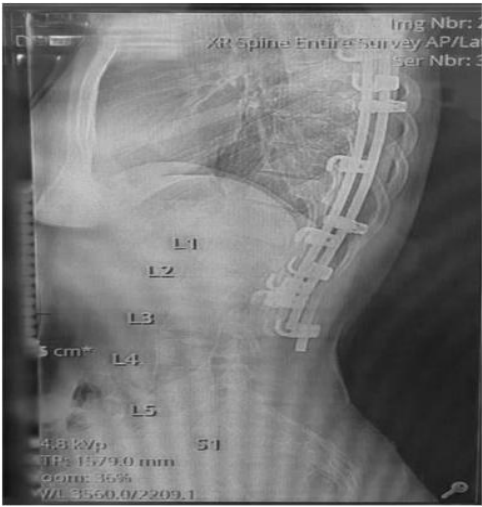

A 26-yr-old gravida 2, para 1 woman was referred by her obstetrician to the pre-anaesthesia assessment clinic at 38 weeks gestation for evaluation. The patient was very keen to know whether she would be able to receive an epidural for labour analgesia. She had a history of severe congenital scoliosis which was corrected at 13 years of age with posterior instrumentation (Fig 1). She had on-and-off complaints of low back pain with shooting pain in her right leg. Her previous normal vaginal delivery was managed with intramuscular pethidine as the patient was denied epidural labour analgesia. On examination, she weighed 73.3 kg with a height of 155 cm (body mass index 30.5 kg/ m2). The patient's back had a long scar running in the thoracolumbar region. However, on palpation of her spine no useful landmarks could be identified. Ultrasound was done in the pre-anaesthesia clinic and L4-L5 and L5- S1 interspaces could be identified.

Fig 1

MRI of the spine revealed posterior corrective surgery with metallic implants from D4 down to L3 with preserved vertebral bodies and alignment with residual thoracolumbar scoliosis.

Figure 1